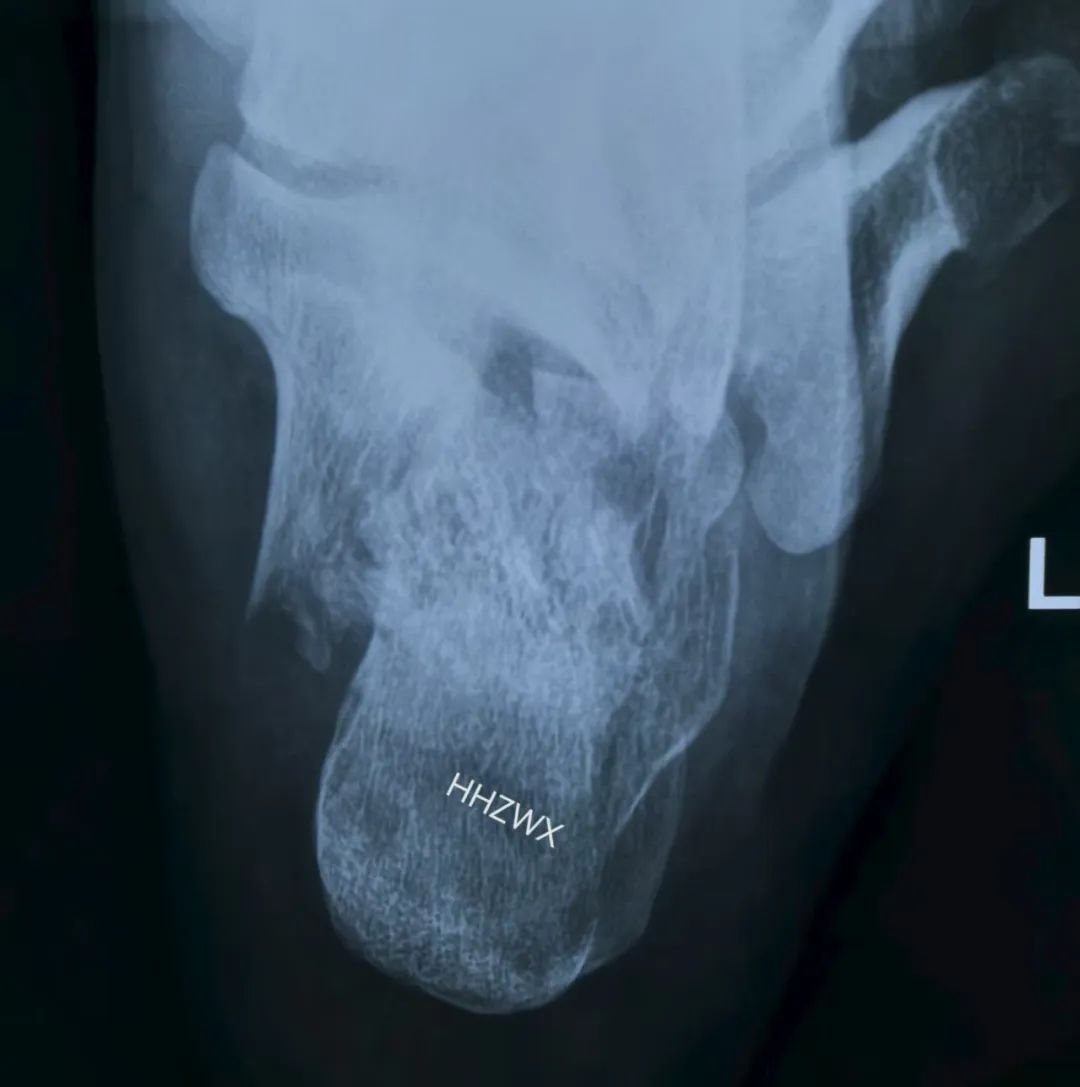

这是一例比较复杂的跟骨,合并舌型骨折块,同时内侧嵌插严重,关节面塌陷。

术中采取打开内侧壁后结合术中骨刀撑开合并上述手法复位内翻,然后给予克氏针固定与稳定的载距突,达到矫正并稳定内翻复位。(很多人复位位置很好,但总是固定不住,最主要的原因就是没有固定骨折块于稳定的骨折块上,固定于载距突可以很好的解决这个问题)

解决内翻之后,复位关节面,同时复位G角和舌型骨折块,辅助克氏针临时固定,可以很好的固定骨折。术中可以看到解剖复位。